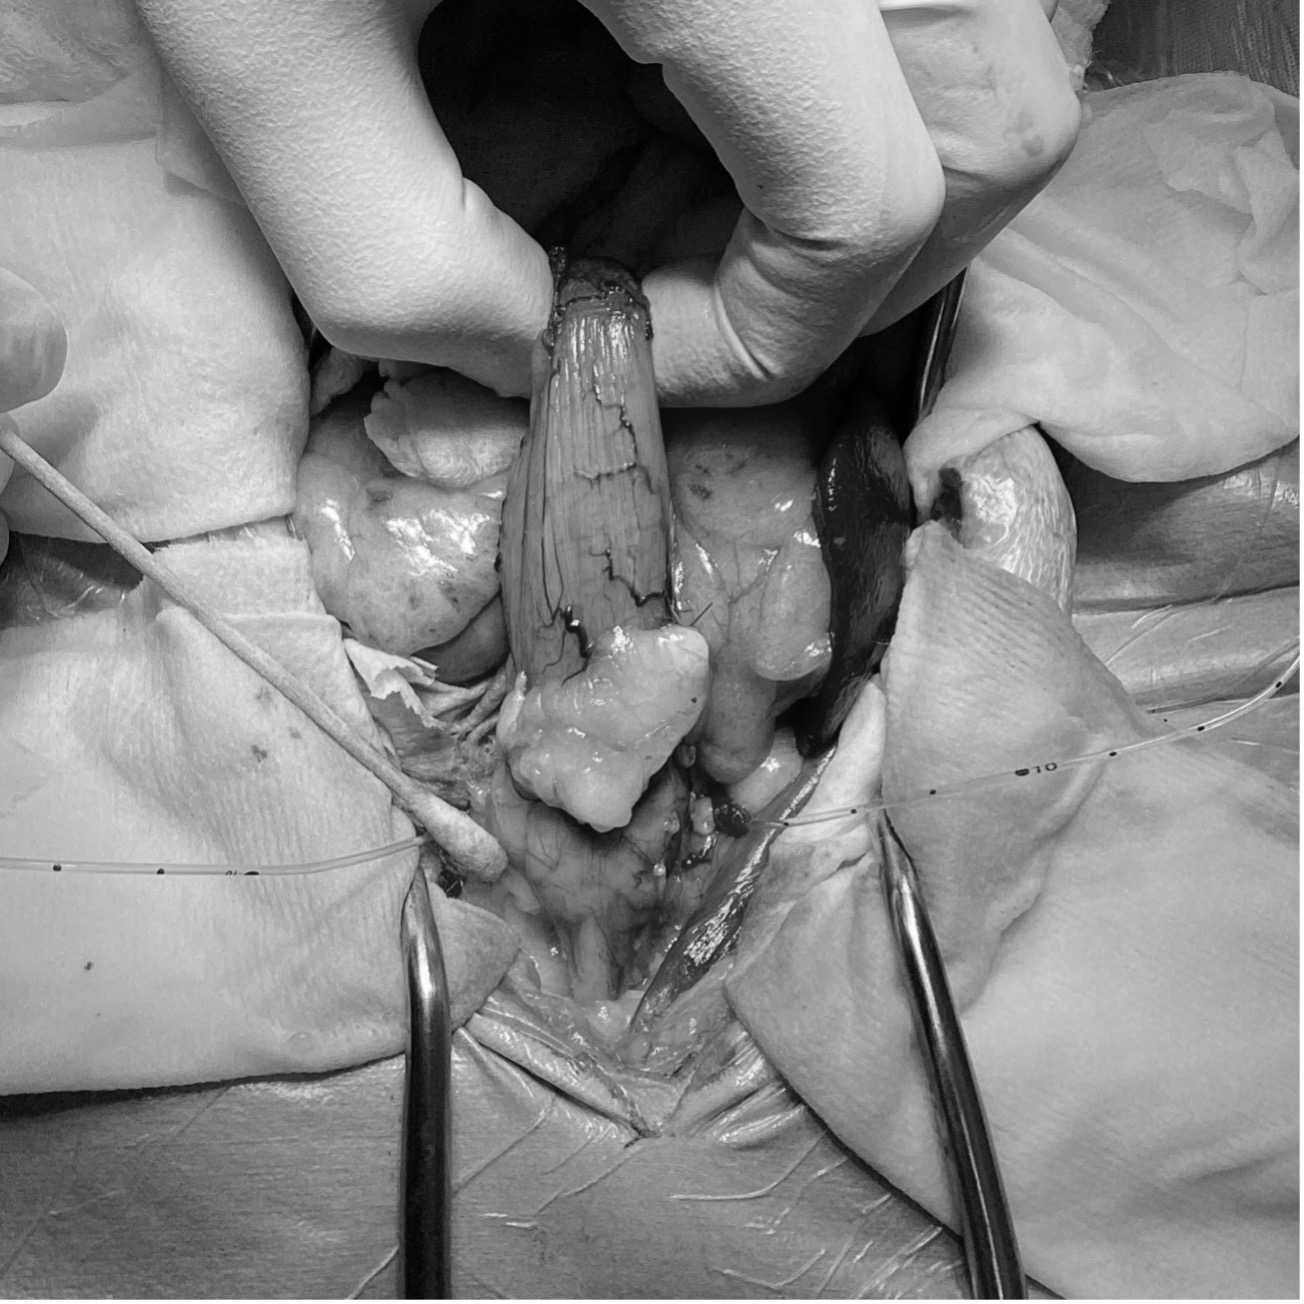

第24病日手術を実施した。胸骨剣状突起から恥骨前縁までの腹部正中切開を行い膀胱、前立腺へアプローチした。左右の尿管を確保し、膀胱移行部を露出後膀胱の近位で左右尿管を離断した。その後尿管にカテーテルを挿入し保持した。膀胱と前立腺、近位尿道を周囲脂肪組織から剥離し、前後膀胱動脈、前立腺動脈を処理し、最後に前立腺から十分距離を確保して尿道を骨盤腔内で結紮離断した。その後、左右尿管を腹壁に造瘻した孔を貫通させ、包皮外側の皮膚に縫合した。(図3,4)術後は左右尿管移設部位にカテーテルを留置し、入院管理を行った。入院5日目にカテーテルを抜去し、尿管移設部位からの尿排出を確認した後に退院となった。病理検査結果は、尿路上皮癌(移行上皮癌)完全切除であった。術後14日目に抜糸を行い、同日ラパチニブを開始した。またNSAIDsとしてフィロコキシブを併用した。 経過は良好であり、ラパチニブ開始から6ヵ月後に再発や転移が認められなかったことから、ラパチニブとフィロコキシブを中止し、現在術後約1年が経過するが再発や転移は認められていない。